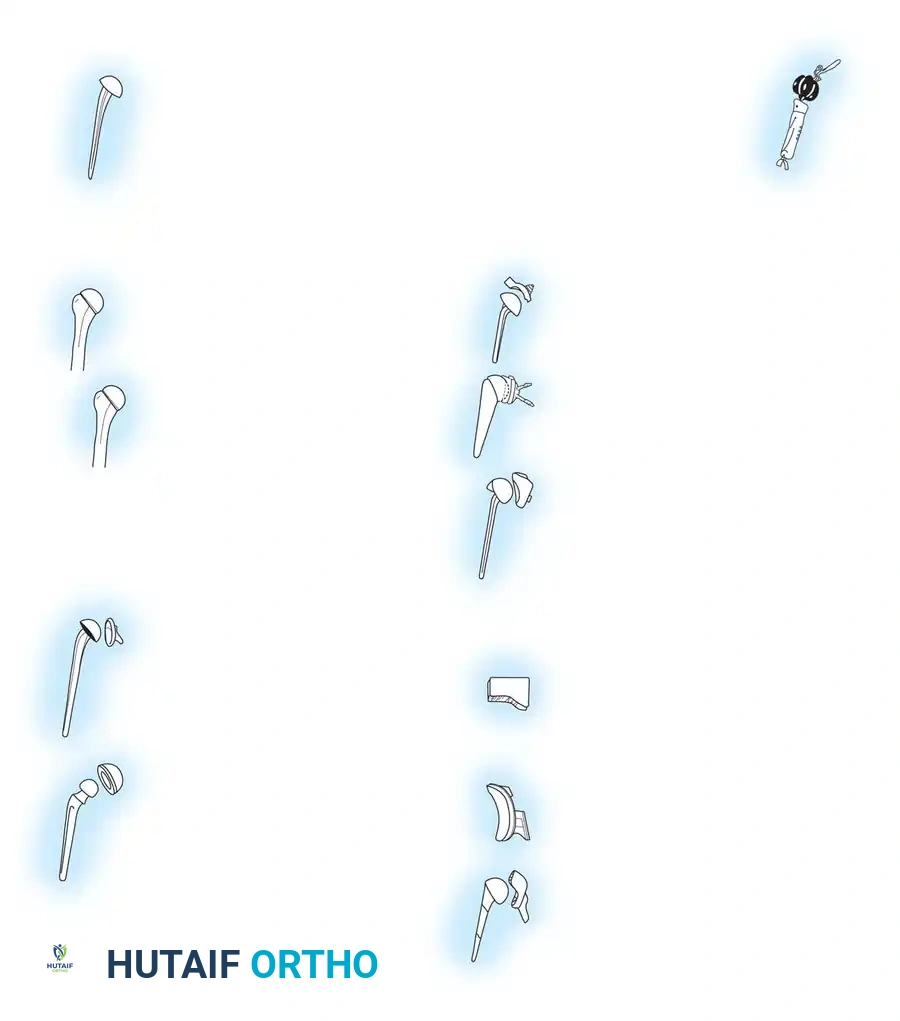

The genesis of shoulder arthroplasty dates back to 1893 when French surgeon J.E. Péan implanted a platinum and rubber prosthesis for a glenohumeral joint destroyed by tuberculosis. Modern shoulder arthroplasty, however, was pioneered in the early 1950s by Charles S. Neer II, who introduced an unconstrained cobalt-chromium alloy (Vitallium) humeral head prosthesis for complex proximal humerus fractures.

By 1974, Neer developed the Neer II humeral prosthesis, modifying it to conform to a high-density polyethylene glenoid component, thereby birthing the modern Total Shoulder Arthroplasty (TSA).

In the 1990s, emphasis shifted toward restoring normal kinematics through modular humeral components, allowing surgeons to replicate individual patient anatomy. Today, the Reverse Total Shoulder Arthroplasty (rTSA), based on the biomechanical principles of Paul Grammont, dominates the landscape for patients with rotator cuff deficiency.

Surgical Technique: Anatomical Total Shoulder Arthroplasty

Reverse Total Shoulder Arthroplasty (rTSA)

Elbow Arthroplasty

Types of Elbow Arthroplasty

- Linked (Semiconstrained): The humeral and ulnar components are physically connected via a locking pin. This is the workhorse for most Total Elbow Arthroplasties (TEA), especially in cases of ligamentous insufficiency or severe bone loss.

- Unlinked: Relies entirely on the patient's native collateral ligaments and soft tissue envelope for stability. Rarely used today due to high rates of instability.